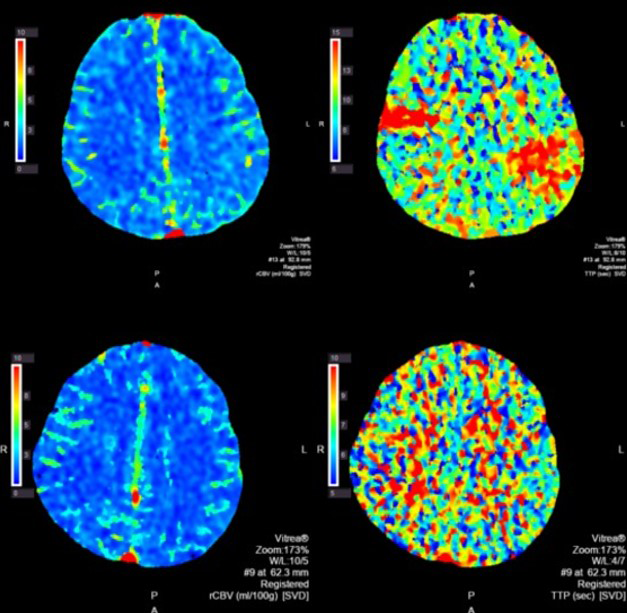

A non-contrast head CT did not demonstrate hemorrhage; however, intravenous rt-PA was held as PTT was elevated at 63 seconds. Further head imaging revealed a 6 mm filling defect in the left M2 branch and a smaller right M3 occlusion (Figure 1). CT Perfusion done at the time demonstrated a moderate left posterior frontoparietal area of perfusion mismatch along with a smaller right frontal area of perfusion mismatch (Figure 2).

Figure 2 CT perfusion images. Top panel was done at onset of symptoms demonstrating elevated left frontoparietal elevated time to peak with relatively preserve cerebral blood flow. A smaller right MCA perfusion deficit can be seen as well. Following thrombectomy this perfusion deficit has now resolved, as seen in the bottom panel.

Post-procedural the patient was noted to have improved somewhat with a largely expressive aphasia, continued gaze preference, and facial droop. Transcranial Doppler microeboli monitoring done post-thrombectomy day 0 revealed multiplemicroembolicsignals during 1 hour of monitoring. A repeat CT Perfusion study done on post-thrombectomy day 1 revealed resolution of left MCA territory mismatch. Unfortunately, on post-intervention day 2 the patient developed a dense left hemiplegia. CT perfusion study demonstrated a large right MCA territory matched defect. The patient was supported medically following this event with care subsequently withdrawn.